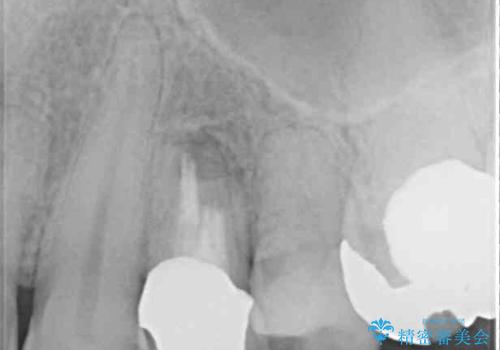

- 他院で抜歯が必要と診断され、再度診断を希望して来院された患者様です。

顕微鏡下で診察を行ったところ、歯根が垂直に破折していたため、抜糸してインプラントによる補綴治療を行うこととしました。